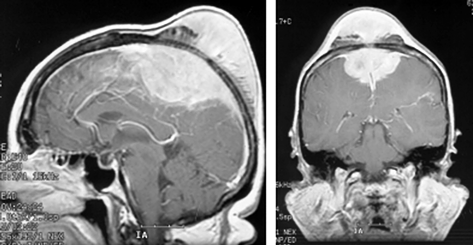

Менингиомы площадки основной кости (рис. 4)

Рисунок 4. Менингиома площадки основной кости. МРТ, Т2-взвешенные изображения, КТ (слева внизу) с контрастным усилением

Менингиомы бугорка турецкого седла

Рисунок 5. Менингиома бугорка турецкого седла. МРТ, Т1 (вверху) и Т2 (внизу) — взвешенные изображения